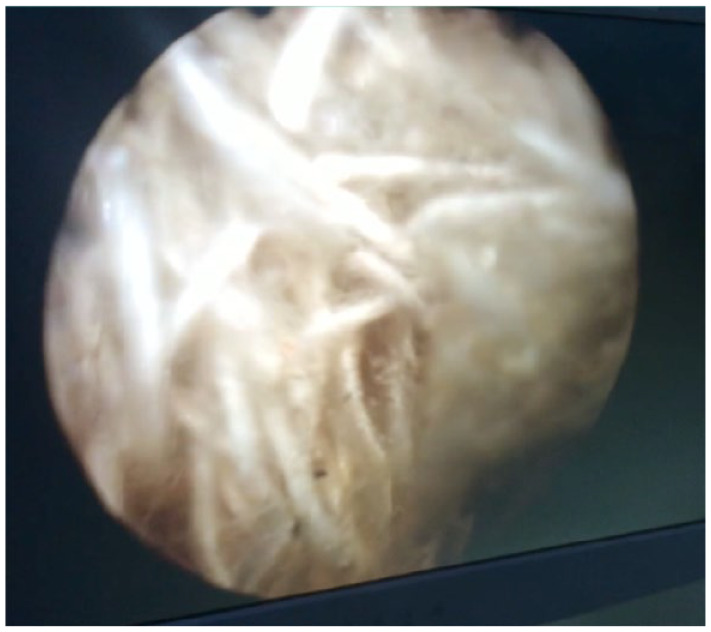

Case presentation: We report a case of intravesical textiloma, rarely observed in urological surgery, in an 80-year-old patient who underwent laparoscopic inguinal hernia repair and presented to a urological consultation with hematuria and irritative lower urinary tract signs. Abdominal ultrasound revealed a hyperechoic tissue-like formation in the posterior wall of the bladder. The diagnosis of a bladder tumor was therefore raised, and cystoscopy was performed, which revealed an intravesical textiloma. All foreign bodies were removed endoscopically, and the patient had a good post-operative outcome.